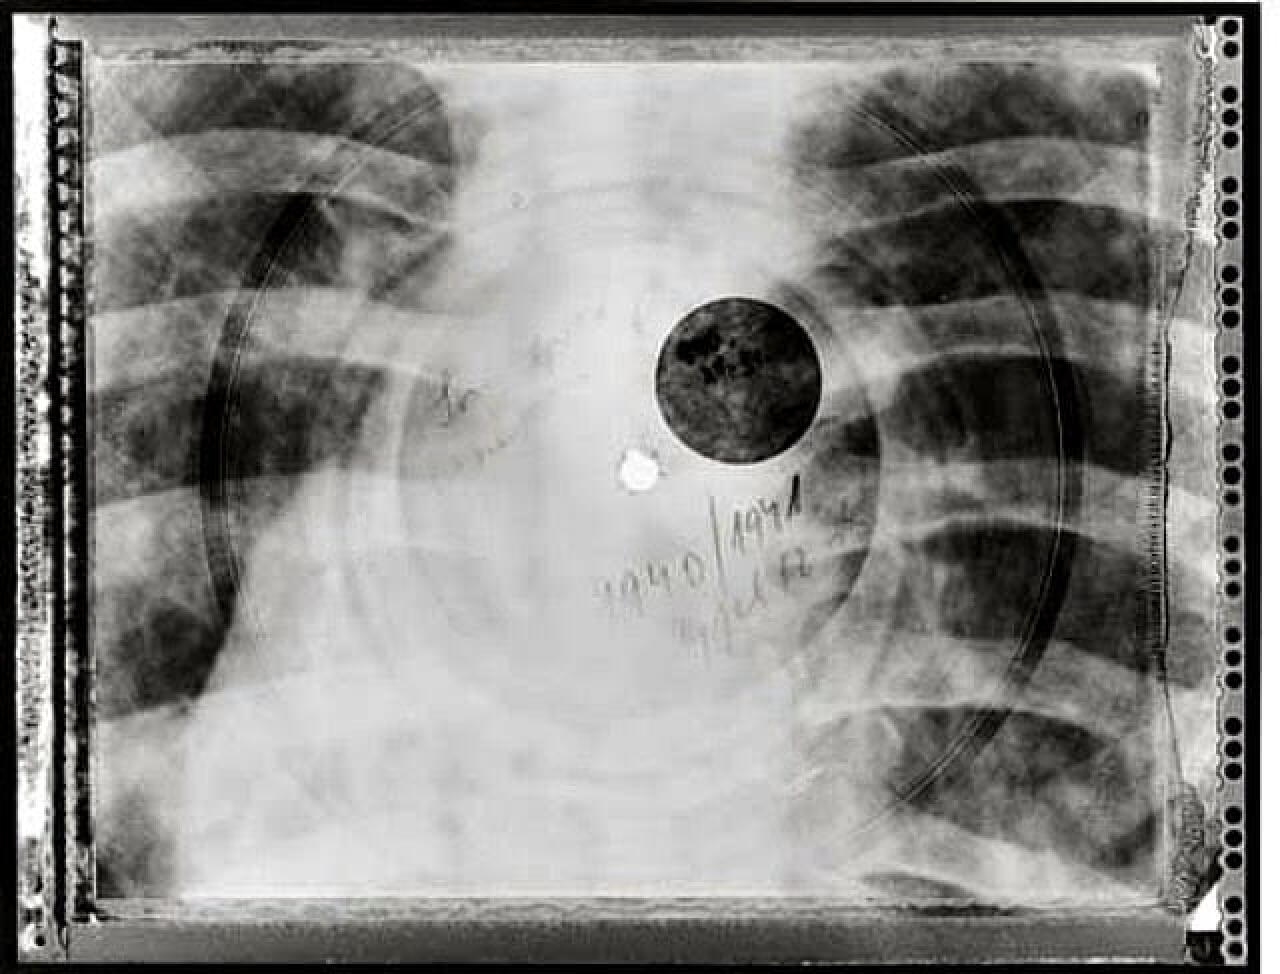

En URSS, les amateurs de jazz et de rock pressaient leurs disques sur des radiographies.

Ils se servent en effet d’anciennes radio pour presser la musique : les zazous de l’époque (qu’on appelle stiliaguis) volaient ainsi les radiographies dans les hôpitaux, et gravaient grâce à des phonographes et en trouant les radios avec une cigarette ce que l’on appelle des « Bones ». Ainsi, avec Elvis sur le poumon, Duke entre les côtes, la musique pouvait circuler en très mauvaise qualité mais à un prix dix fois inférieur à celui des marchés occidentaux. Aujourd’hui, il reste de cette période ces radios qui sont presque de véritables oeuvres d’art.